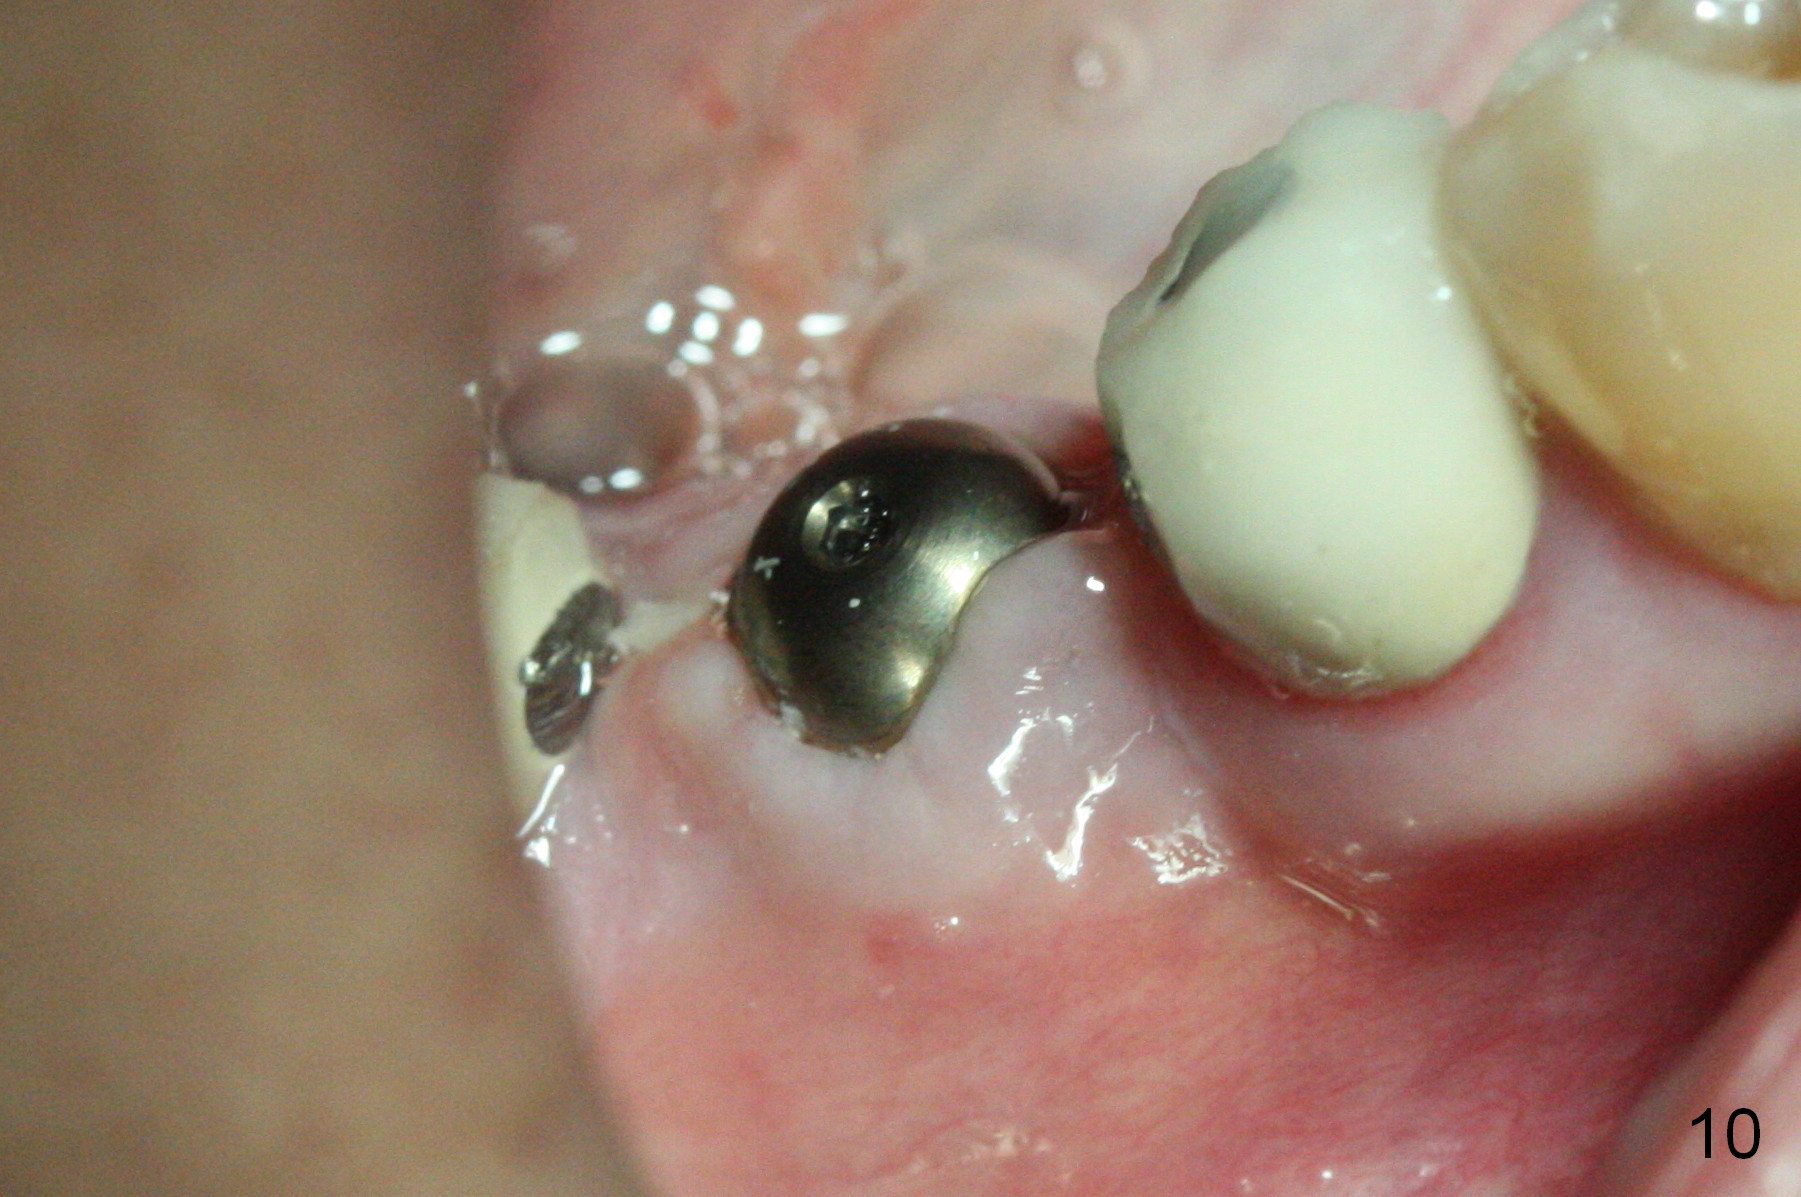

The wound is healing 8 days postop (Fig.10). Because of the short cuff (subgingival margin), screw retention type of restoration will be used, in contrast to cement type of the 2nd case. In fact, FC one is used.